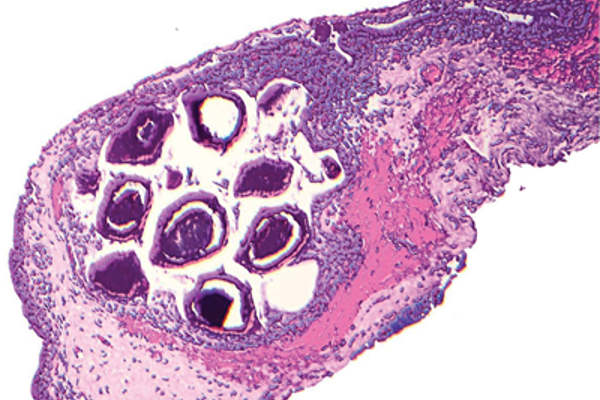

Pathology Quiz - Section Editor until Aug/Sep 2016